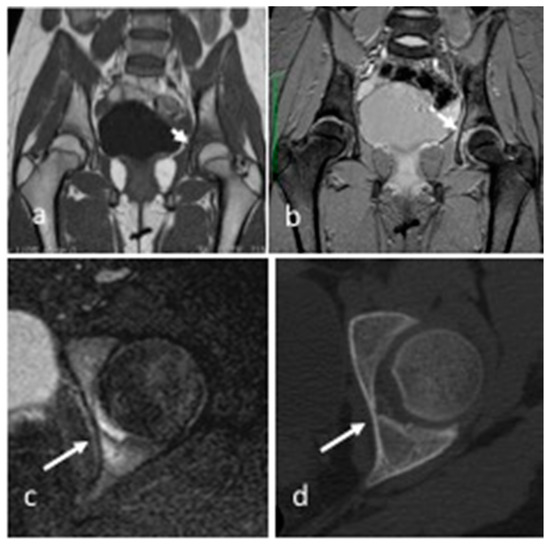

| 8 | F | 14 | right humerus, olecranon fossa, intra-articular cortical | pain, right elbow | yes | yes | yes | yes | yes | 9 | post-traumatic arthritis | CT-guided RFA |

| 9 | M | 15 | right second toe, distal phalanx, juxta-articular cortical | swelling and pain, second toe | yes | no | yes | yes | no | 12 | psoriatic arthritis | surgery resection |

| 10 | F | 5 | pedicle L1, intra-articular cortical | back pain, scoliosis | yes | yes | no | - | yes | 2 | traumatic vertebral fracture | surgery resection |